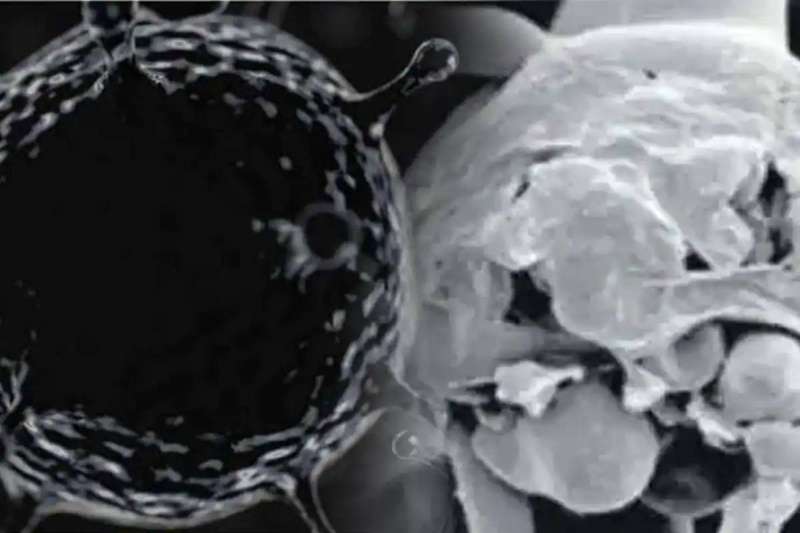

الفطر الأبيض أخطر من الأسود!

هذا ما كشفته صحيفة «إنديان إكسبريس» الهندية في تقرير أصدرته أمس، عن ظهور مرض الفطر الأبيض في البلاد، وهو أكثر خطورة وأشد فتكاً من نظيره الأسود.

ما هو «الفطر الأبيض»؟

ناتج عن خميرة (نوع من الفطريات) تسمى المبيضات، والتي يمكن أن تعيش بشكل طبيعي داخل الجسم، في مناطق مثل الفم والحلق والأمعاء، من دون التسبب في أي مشاكل.